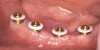

Figure 6A  An implant-retained and tissue-supported two-implant overdenture system.

Figure 6A

Figure 6B An implant-retained and tissue-supported two-implant overdenture system.

Figure 6B